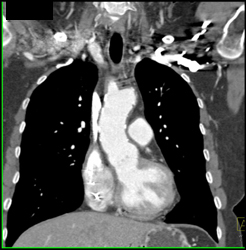

Diagnosis

Type B Dissection